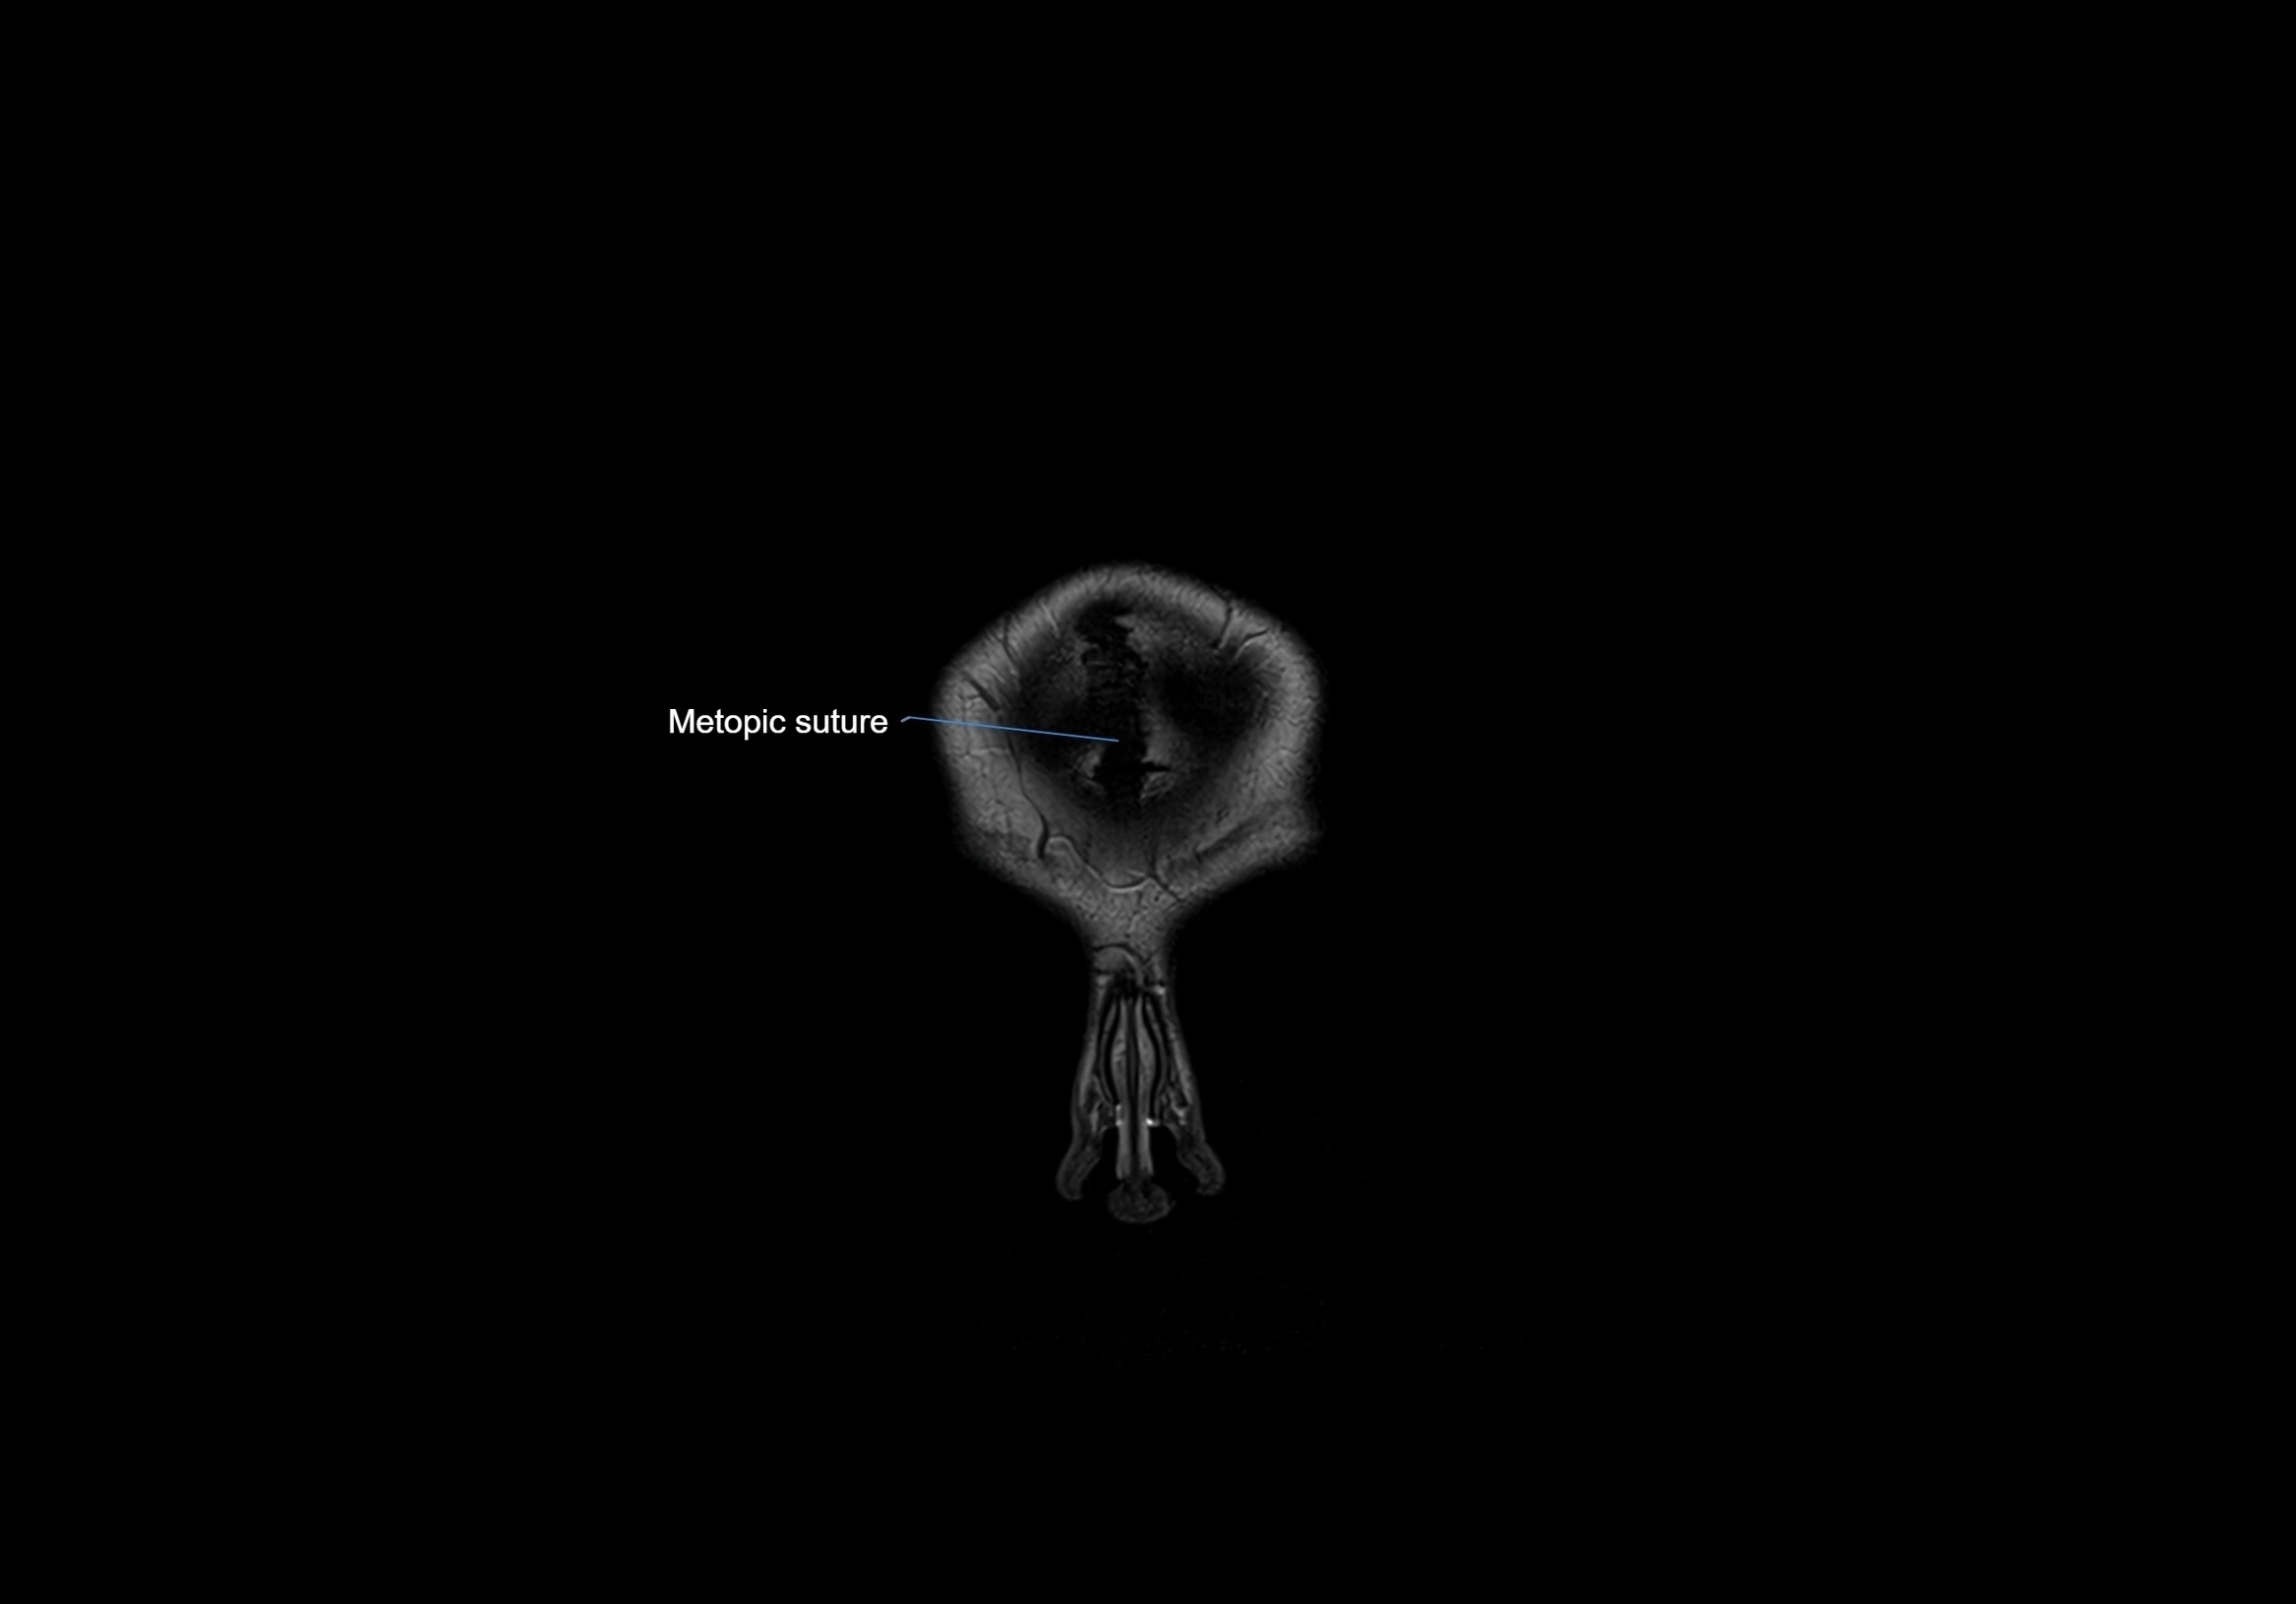

- Frontal suture